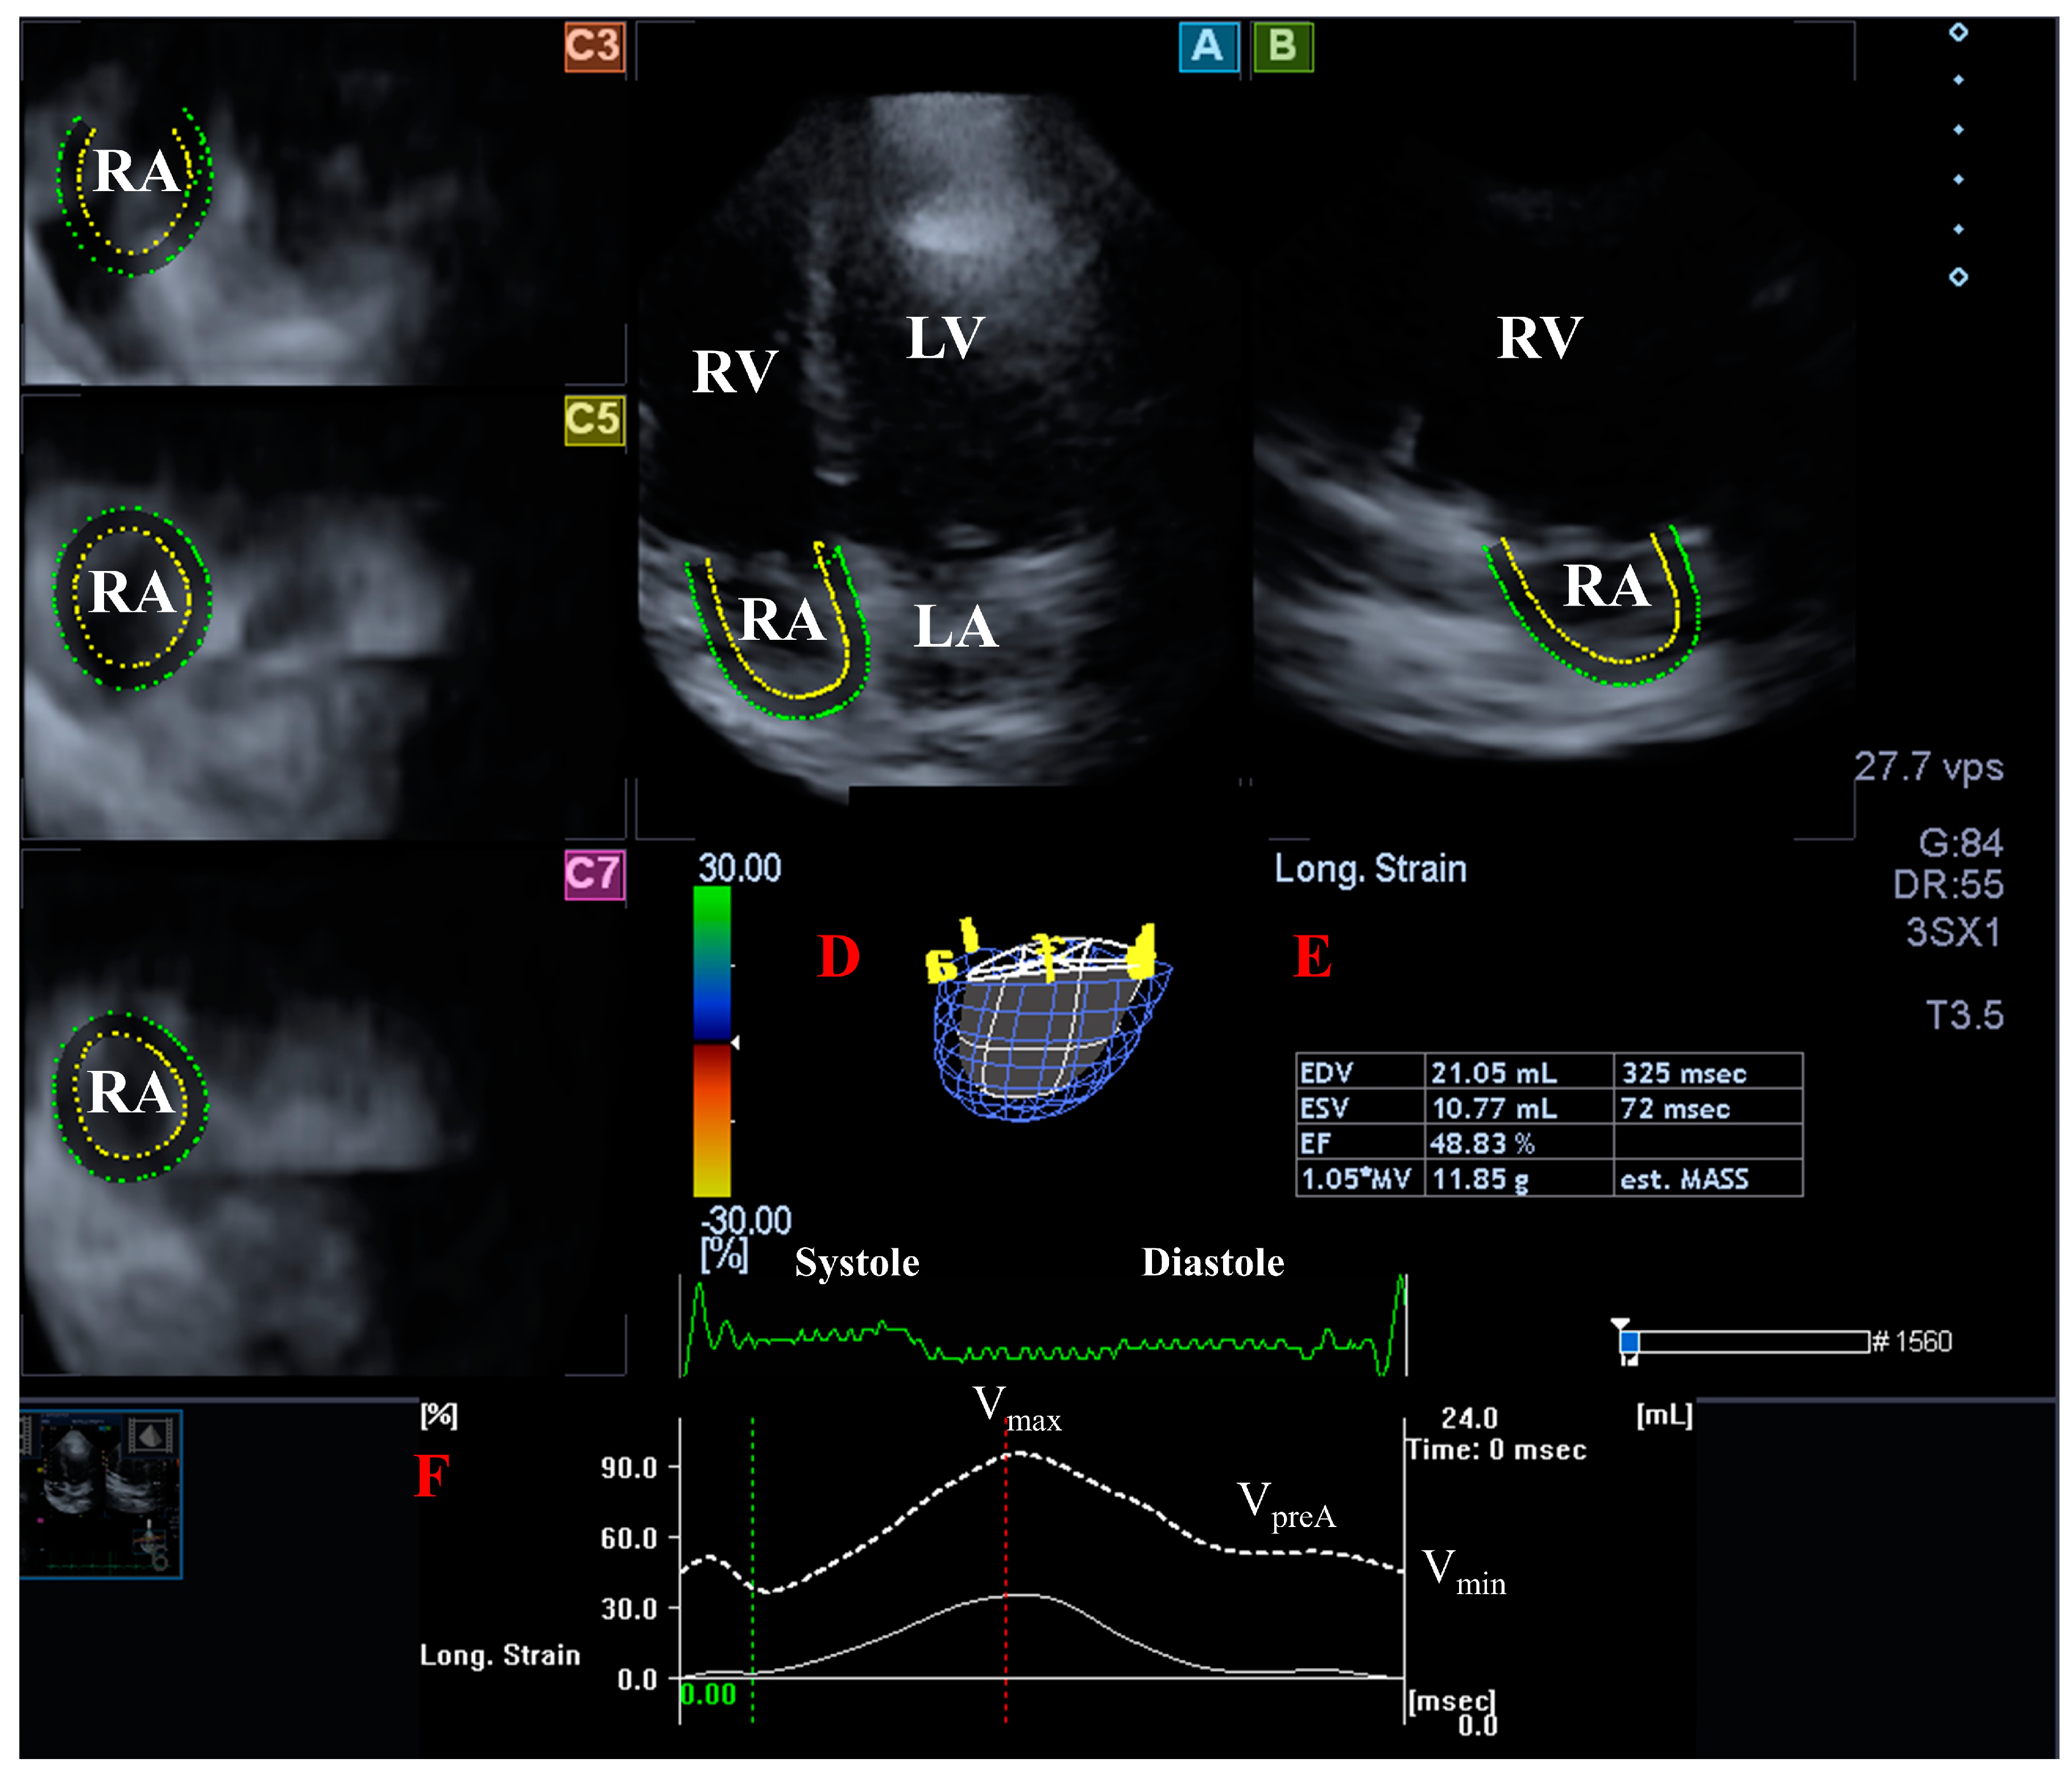

- TA diameter (TAD) was defined as the perpendicular line drawn from the peak of TA curvature to the opposite side of the TA border;

- TA area (TAA) was assessed by planimetry;

- TA perimeter (TAP) was evaluated by planimetry;

- TA fractional shortening (TAFS) = [end-diastolic TAD − end-systolic TAD]/end-diastolic TAD × 100;

- TA fractional area change (TAFAC) = [end-diastolic TAA − end-systolic TAA]/end-diastolic TAA × 100.

- Nemes, A.; Kormányos, Á.; Domsik, P.; Kalapos, A.; Ambrus, N.; Lengyel, C. Normal reference values of three-dimensional speckle-tracking echocardiography-derived right atrial volumes and volume-based functional properties in healthy adults (Insights from the MAGYAR-Healthy Study). J. Clin. Ultrasound 2020, 48, 263–268. [Google Scholar] [CrossRef]

- Nemes, A.; Kormányos, Á.; Rácz, G.; Ruzsa, Z.; Ambrus, N.; Lengyel, C. Normal reference values of tricuspid annular dimensions and functional properties in healthy adults using three-dimensional speckle-tracking echocardiography (insights from the MAGYAR-Healthy Study). Quant. Imaging Med. Surg. 2023, 13, 121–132. [Google Scholar] [CrossRef]